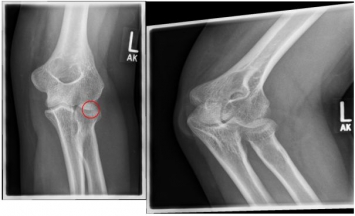

Ellenbogen

Photo: An undislocated fracture that can be treated conservatively.